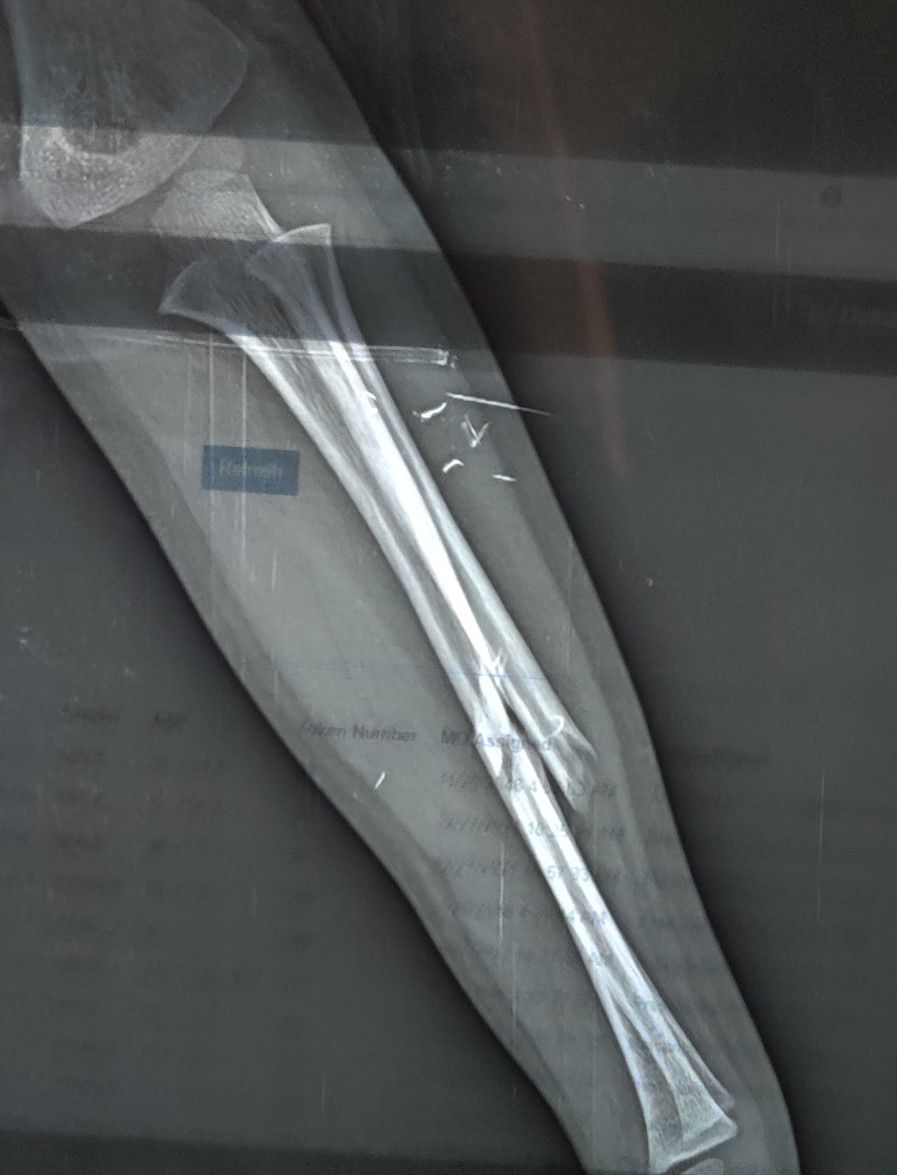

Radius + Ulna Fracture

Fracture

Radius

Ulna